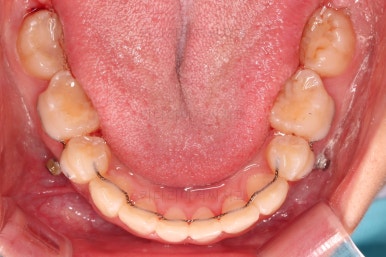

교합, 과개교합 모두 좋아졌고요.

발치 공간도 깔끔하게 닫히고 종료했습니다.